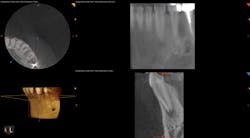

To determine whether tooth No. 21 or No. 22 was the issue, two periapical radiographs were taken. However, the results were inconclusive (figures 2–4). With clinical testing and 2-D radiographs providing no smoking gun, it was decided to use limited field-of-view CBCT (Carestream Dental CS 9000C 3D) on the region. CBCT revealed that tooth No. 22 was abscessed and a fair amount of the apical bone was completely gone (figures 5 and 6). In fact, since the time the pain began and when the patient presented at the practice, the tooth had abscessed at an alarming rate and was now considered an emergency situation.

Figure 5: CBCT showing the periapical lesion on No. 22 in multiple slices on the lower right-hand side of the image